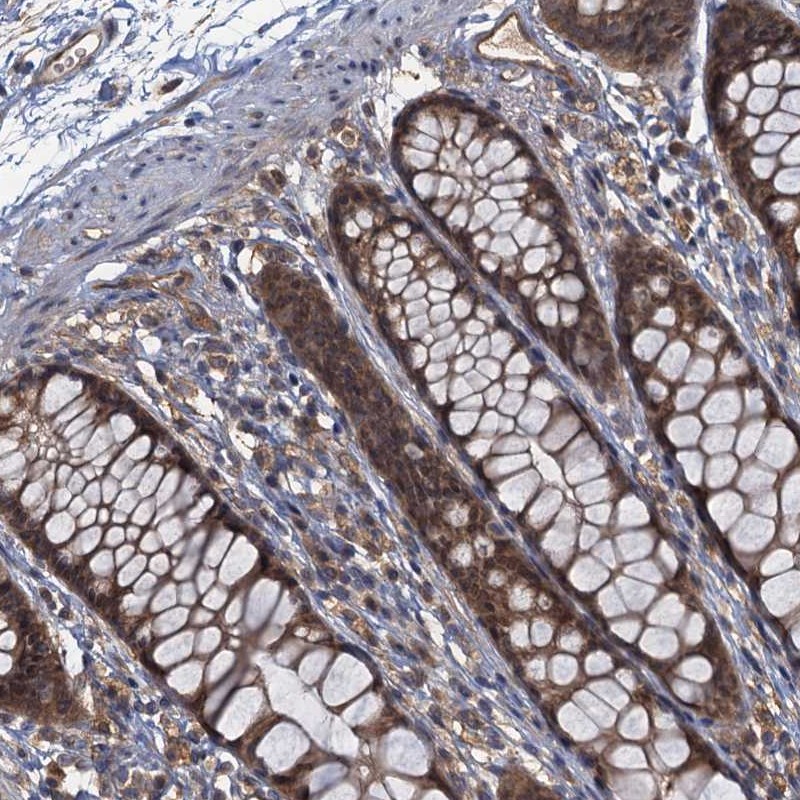

Immunohistochemical staining of human rectum shows moderate cytoplasmic and nuclear positivity in glandular cells.